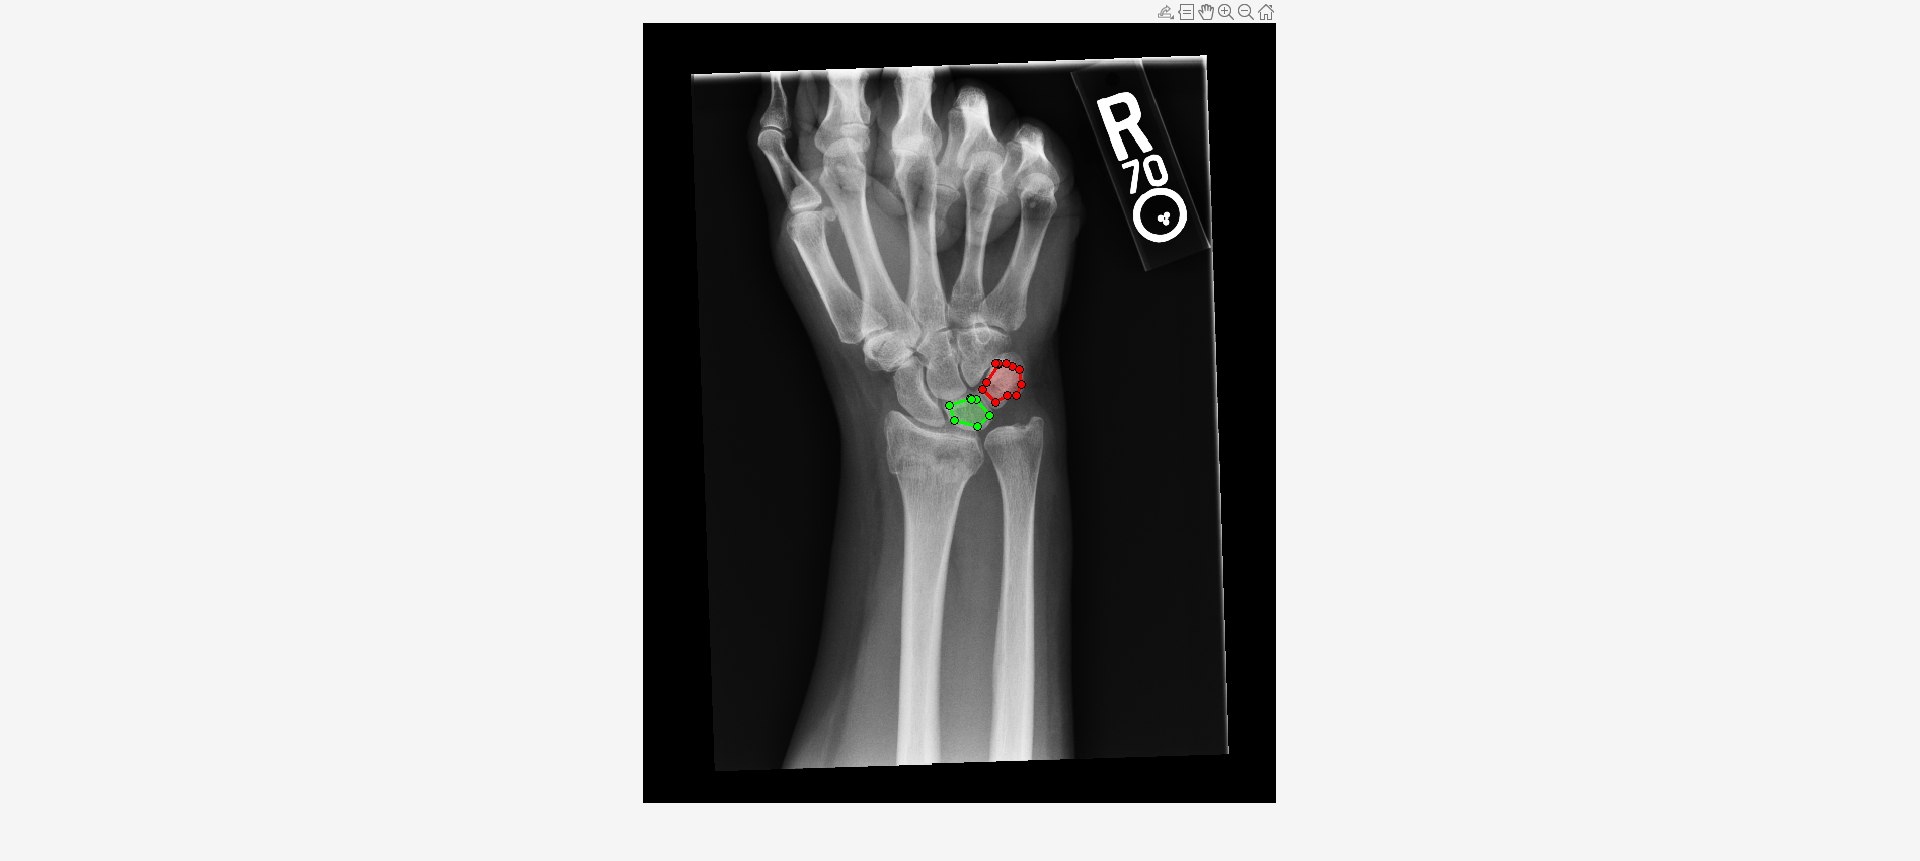

Load an X-ray image into the workspace as a medicalImage object. Visualize the image.

data = medicalImage("forearmXrayImage1.dcm");

I = data.Pixels;

figure

imshow(I,[])Draw two regions of interest (ROI) in the X-ray image. Create masks from the ROIs.

roi1 = drawassisted(Color="g"); roi2 = drawassisted(Color="r");

mask1 = createMask(roi1,I); mask2 = createMask(roi2,I);

Create an ROI label matrix, using different labels for the two ROIs. Create a medicalImage object of the ROI label data.

mask = zeros(size(I));

mask(mask1) = 1;

mask(mask2) = 2;

info = dicominfo("forearmXrayImage1.dcm");

roi = medicalImage(mask,info);Create a radiomics object from the X-ray image data and ROI label data.